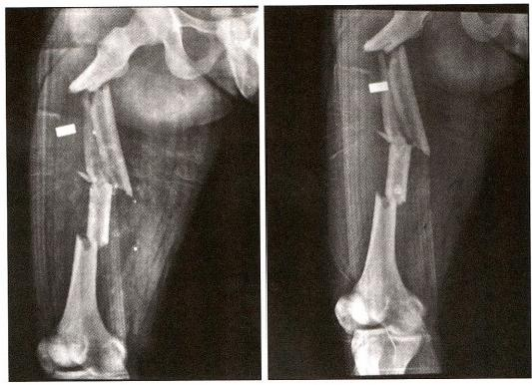

患者为严重粉碎性骨折,股骨转子下+中段骨折,LambirisⅡ 型 ( 图 12-2)。

图12-2 严重粉碎性骨折,股骨转子下+中段骨折,LambirisⅡ型